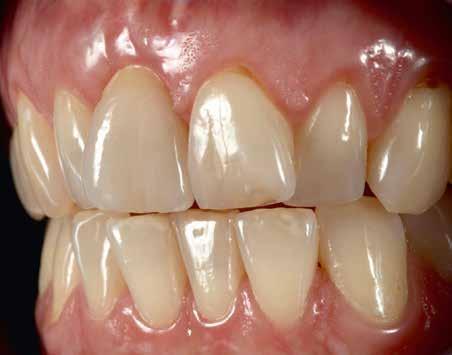

Elhagyott frontfogak, megtámadott parodoncium: a páciens kiindulási helyzete több mint nehéznek bizonyult. Yuki Momma és dr. William C. Heggerick, szerzőink, bemutatják, hogyan állítható helyre a harmónia a négy frontfog ellátásával.

A felső frontfogak állapota elhanyagolt, a parodontális struktúrák részben erősen károsodottak, VMK korona az 12 zónában, az ínyszél szürke, fekete approximális háromszögek… vörös-fehér esztétikáról nem is beszélhetünk (1. kép). Így jelentkezett a hölgypáciens a Weston Dental Specialists Group rendelőben. Elvárásai magasak voltak. A defektusok kezelését, a gingiva lefutásának korrigálását kívánta. Gyorsan világossá vált, hogy a megoldást csak a négy frontfog teljes kerámiakoronával való ellátása jelentheti. A jelen eset bemutatja, hogy az IPS e.max ZirCAD Prime segítségével hogyan lehet tiszta, tetszetős és esztétikus mosolyt létrehozni.

1. kép: Kiindulási helyzet.

A kialakítás tervezése

A páciens aggodalmas volt, hogy ne kapjon túl nagy és szögletes koronákat. A vele folytatott megbeszélések során viaszmintázat, majd annak alapján kulcs készült a mock-uphoz. Ennek segítségével az újonnan készülő pótlás formáját közösen, egyértelműen határozhattuk meg (2. kép).

Anyagválasztás

A koronákat IPS e.max ZirCAD Prime (Ivoclar Vivadent) anyagból martuk ki. E cirkónium-dioxid korongok előállítása Gradient Technology (GT) segítségével történik, az alap-

anyag egyidejűleg nagy szilárdságú és transzlucens is. Ez több szempontból előnyös: először is adott a jó stabilitás – a biaxális hajlítószilárdság 1200 Mpa, a törési szilárdság nagyobb 5 Mpa m1/2-nál. Ezzel hosszú élettartamú koronák és nagy fesztávolságú hidak készítésére is alkalmas. Ugyanakkor a kerámia teljesen fokozatmentes színátmenettel és nagyfokú transzlucenciával is rendelkezik, így bevethető a magas esztétikájú frontpótlások területén is. A megoldandó esettől függően teljes, részben vagy egészen leplezett formában is alkalmazható, akár egy pótláson belül kombinálva. Ezáltal az IPS e.max ZirCAD Prime valóban „One-Disc-Solution” (egy korong mindenre megoldás – a ford.), amelynek előnyeit maximálisan kihasználhatjuk minden páciens számára. Ebben az esetben enyhén redukált koronavázakat alakítottunk ki, amelyet az IPS e.max ZirCAD Colouring Liquids, az IPS e.max Ceram leplezőrendszere, valamint festék- és glazúrkészlete segítségével egészítettünk ki (3–7. képek).

oka a zománcvastagság változása cervikáltól incizál felé. A dentin, amely erőteljesebb színtelítettségű, mint a zománc, változó erősséggel tűnik át a háttérből, és tipikus karaktert kölcsönöz a fognak. Az 12-es fogon látható VMK korona (fémkerámia – a ford.) nem felelt meg ezeknek a követelményeknek, és élettelen testként tűnt fel a front megjelenésében. A 8. kép az IPS e.max ZirCAD Prime koronák próbájánál készült. Jól látható, hogy a folyamatos szín- és transzlucencia átmenet ideálisan imitálja a természetes fogakét, és plasztikus benyomást kelt. Az egyedi jellegzetességek, mint

4. kép: A szinterezett koronák a mintán.

6. kép: Az első égetés köztes eredménye.

8. kép: A próba.

a mamelonok és a kiemelt zománcrepedések élettelibbé teszik a koronákat.

Gingivára fókuszálás

A gingiva kontúr lefutása szintén fontos az esztétikus megjelenés szempontjából. A teljesen szimmetrikus restaurációk általában természetellenesen hatnak, az árkádok itt látható enyhe aszimmetriája természetes hatást

9. kép: A végleges beragasztás.

10. kép: Végeredmény: esztétikus, természetes, szép.

keltett. Az egyébként ideális tipikus formájú koronák esztétikailag optimális gingivakialakítást hoznak létre, a VMK korona kicserélése egyenletes fénytovábbítást tett lehetővé a papilláktól a korona felé és fordítva is. Míg a próba során még minimális sötét approximális háromszögek láthatók voltak, a végleges beragasztásra (Variolink Esthetic, Ivoclar Vivadent) már eltűntek (9. kép). A gingiva tökéletesen hozzásimult az IPS e.max ZirCAD Prime restaurációhoz.

Összefoglalás

Anyagválasztásunk újra tökéletesnek bizonyult. Kiemelkedő természetes hatása folytán akár leplezetlen IPS e.max ZirCAD Prime anyaggal is nagyon jó esztétikai hatású monolit restaurációk készíthetők. Itt az optimális alapot képezte, hogy leplező- és festékanyagainkkal elérhessük a kívánt hatást: hibátlan mosolyt és természetes szépséget. A páciens nagyon elégedett a kezelés eredményével – akárcsak mi magunk (10. kép).